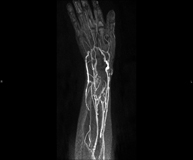

Prueba diagnóstica no invasiva que consiste en el estudio de las arterias de la cintura escapular, brazo, antebrazo y mano obteniendo imágenes de alta definición anatómica mediante el empleo de un campo electromagnético y ondas de radio (con un emisor y un receptor). Es indispensable el uso de contraste intravenoso paramagnético (gadolinio). Sin embargo, no utiliza radiación ionizante. La calidad de las imágenes permite realizar reconstrucciones en 2D y 3D. Está especialmente indicado en aquellos pacientes en los que hay sospecha de enfermedad vascular de ambas extremidades, en pacientes con enfermedad vascular de ambas extremidades como mapa vascular antes del tratamiento (percutáneo o quirúrgico), como mapa vascular pre-quirúrgico en pacientes con lesiones óseas o musculares que requieran cirugía…